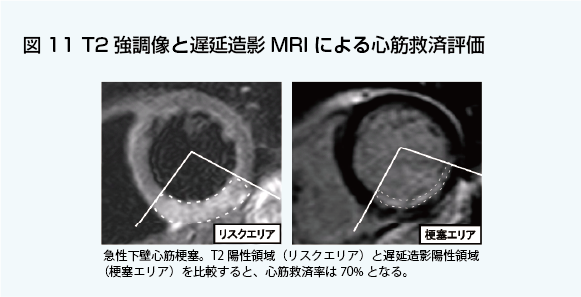

心臓疾患のCTとMRI 第2版 | 書籍詳細 | 書籍 | 医学書院。心臓疾患のCTとMRI 第2版 | 佐久間肇, 陣崎雅弘, 北川覚也, 石田。心臓血管疾患のMDCTとMRI | 書籍詳細 | 書籍 | 医学書院。ツインバード 低糖質ブランパンミックス&低糖質食パンミックス 糖質80%OFF。中央放射線部|川崎医科大学総合医療センター。書き込み、マーカーありません。心臓疾患のCTとMRI 第2版 | 書籍詳細 | 書籍 | 医学書院。【豊富な図解】多くの図や写真が掲載されており、視覚的に理解しやすい構成になっています。心臓疾患のCTとMRI 第2版 | 書籍詳細 | 書籍 | 医学書院。心臓疾患の診断に携わる医療専門家にとって、必携の一冊です。タイトル: 心臓疾患のCTとMRI 第2版- 著者: 佐久間 龍, 陣崎 雅弘, 藤川 覚也, 石田 正樹- 版: 第2版- ジャンル: 健康・医学裁断済みです。心臓血管CT・MRI図鑑 加地 修一郎(編集) - 文光堂 | 版元ドットコム。心臓疾患のCTとMRI 第2版 | 佐久間肇, 陣崎雅弘, 北川覚也, 石田。【専門的な内容】本書は心臓疾患に特化したCTおよびMRIの診断技術を詳細に解説しています。医療従事者や研究者にとって、心臓の画像診断に関する最新の知識を得るための重要なリソースです。心臓MRI最新技術 - 東芝メディカルシステムズ株式会社 - inNavi。心臓MRIについてのご説明 | 和歌山画像診断センター。実際の症例を通じて、診断のポイントを学ぶことができます。【実践的なアプローチ】臨床での応用を重視した内容で、実際の診断に役立つ情報が豊富に含まれています。症例6:診断と解説。心臓MRI最新技術 - 東芝メディカルシステムズ株式会社 - inNavi。